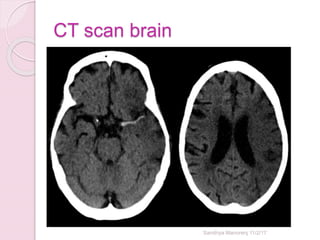

CT scan brain - Stroke

 Ischemic stroke

Sandhya Manorenj 11/2/17

• #35 Early features of left mca ischemic stroke